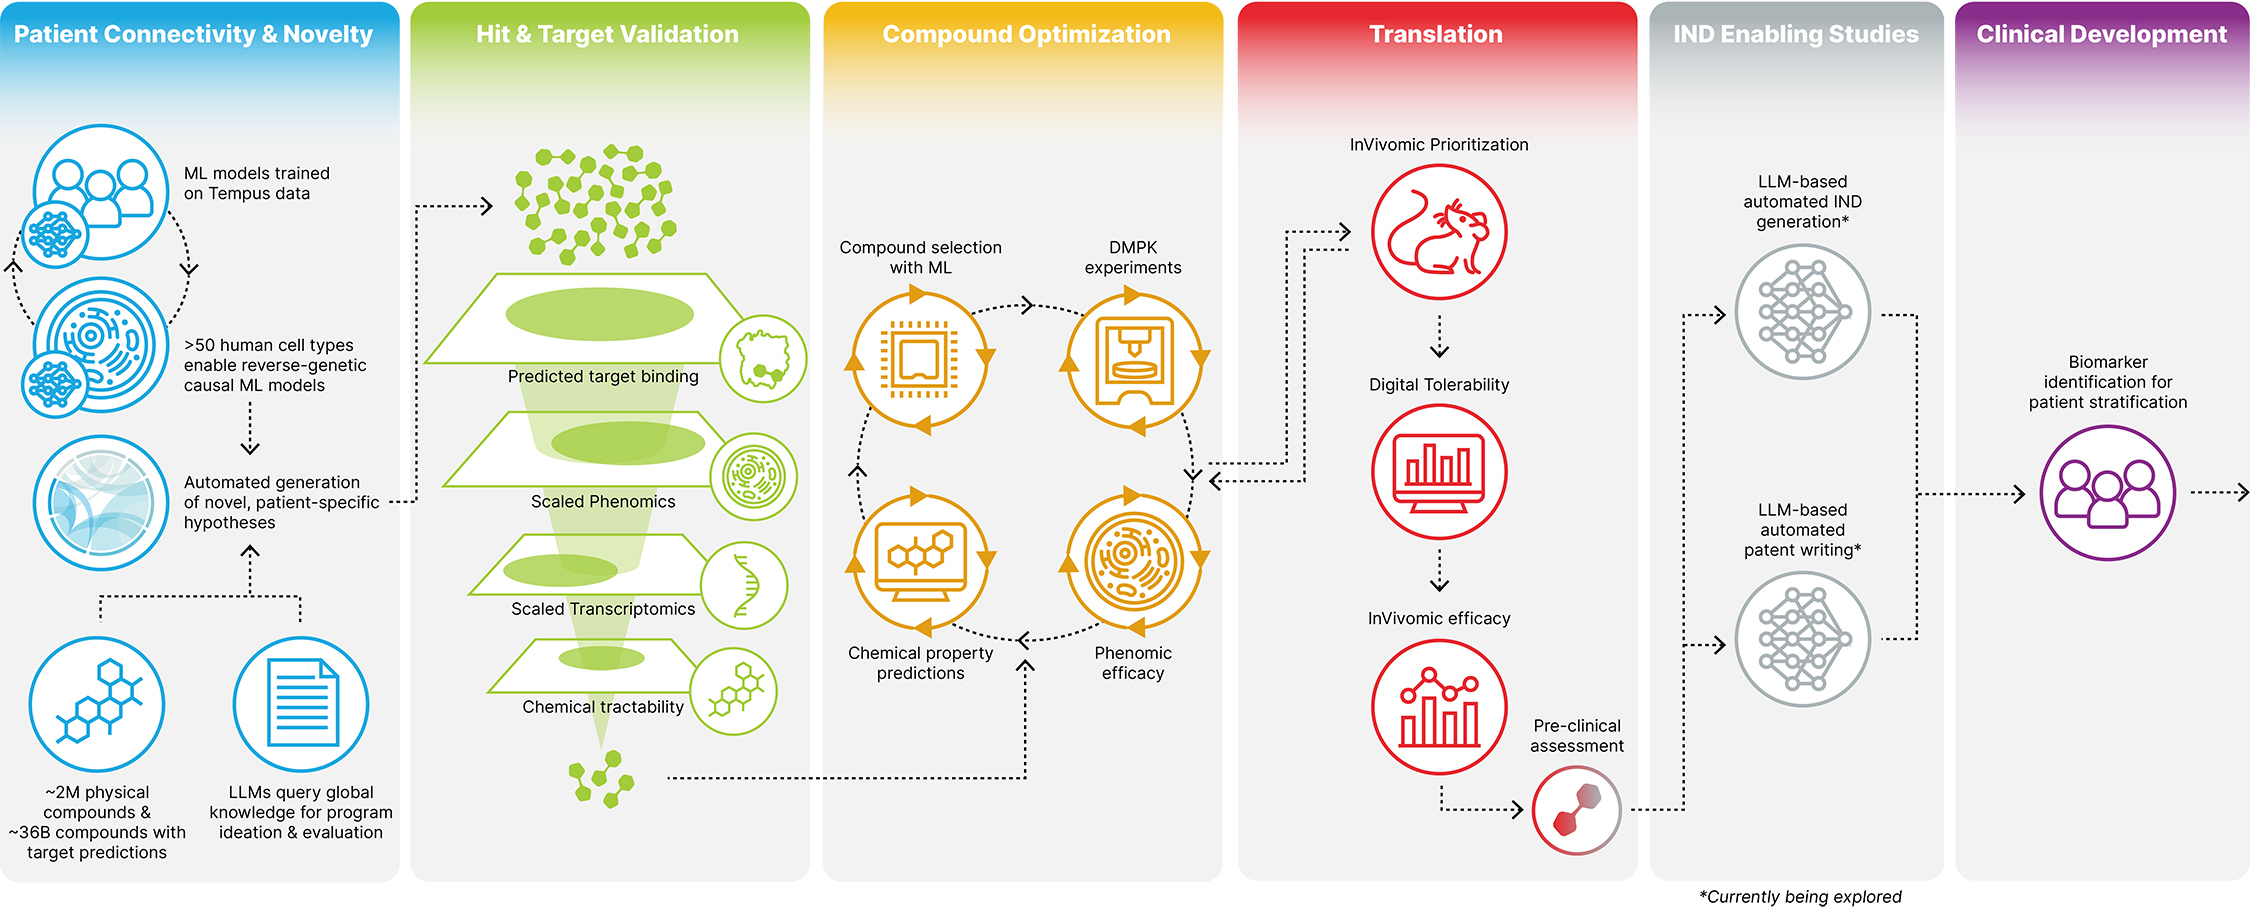

Recursion is a leading clinical stage TechBio company decoding biology to industrialize drug discovery. Central to our mission is the Recursion Operating System (OS), a platform built across diverse technologies that enables us to map and navigate trillions of biological, chemical, and patient-centric relationships across over 50 petabytes of proprietary data. We frame this integration of the physical and digital components as iterative loops, where scaled ‘wet-lab’ biology, chemistry, and patient-centric experimental data are organized by ‘dry-lab’ computational tools in order to identify, validate, and translate therapeutic insights. We believe Recursion’s unbiased, data-driven approach to understanding biology will bring more, new, and better medicines at higher scale and lower cost to patients.

Figure 1. A simple formula is used across technology industries to map and navigate complex systems. First, high-dimensional data is generated, aggregated and organized to create digital representations. Then, AI/ML algorithms make predictions about that system that can be tested in reality. The result is a virtuous cycle of learning and iteration.

How Recursion is Industrializing the Drug Discovery Process

At Recursion, we are pioneering the integration of innovations across biology, chemistry, automation, data science and engineering to industrialize drug discovery in a full-stack solution across dozens of key workflows and processes critical in discovering and developing a drug. For example, by combining advances in high content microscopy with arrayed CRISPR genome editing techniques, we can rigorously profile massive, high-dimensional biological and chemical perturbation libraries in multiple human cellular contexts to create digital ‘maps’ of human biology. Leveraging advances in scaled computation, we can conduct massive virtual screens to predict the protein targets for billions of chemical compounds. Similarly, data generated from our automated DMPK module and InVivomics platform enables us to predict ADME properties and identify toxicity signals, respectively, significantly faster than traditional methods. We believe that by harnessing advances in technology to industrialize drug discovery, we can derive novel biological insights not previously described by scientific researchers, reduce the effects of human bias inherent in discovery biology and reduce translational risk at the program outset.

Figure 6. Recursion’s approach to drug discovery. We utilize our Founding Principles on the right to build datasets which are scalable, reliable and relatable in order to elucidate novel biological and chemical insights and industrialize the drug discovery process.